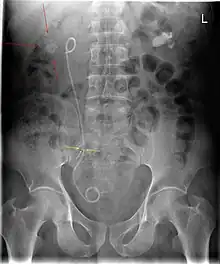

A ureteral stent (pronounced you-REE-ter-ul), or ureteric stent, is a thin tube inserted into the ureter to prevent or treat obstruction of the urine flow from the kidney. The length of the stents used in adult patients varies between 24 and 30 cm. Additionally, stents come in differing diameters or gauges, to fit different size ureters. The stent is usually inserted with the aid of a cystoscope. One or both ends of the stent may be coiled to prevent it from moving out of place; this is called a JJ stent, double J stent or pig-tail stent.